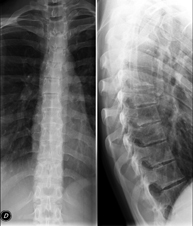

Tècnica que usa els raigs X a través de la qual s'obtenen imatges de la columna cervical per al seu estudi. Indicacions: traumatisme, dolor cervical. - RX Columna dorsal

Tècnica que usa els raigs X a través de la qual s'obtenen imatges de la columna dorsal per al seu estudi. Indicacions: traumatisme, mal d'esquena. - RX Columna lumbar

Tècnica que usa els raigs X a través de la qual s'obtenen imatges de tota la columna vertebral per al seu estudi, amb la valoració especialment de la presència d'escoliosi i dismetries pèlviques.

Una radiografia d'abdomen és una tècnica mitjançant la qual, amb l'ús d'una petita dosi de radiació, s'obté una imatge bidimensional de l'abdomen amb les seves estructures anatòmiques (estómac, intestí prim, intestí gros, fetge, pàncrees, ronyons, bufeta, pelvis òssia, etc.) - Telerradiologia columna

Tècnica que usa els raigs X a través de la qual s'obtenen imatges de tota la columna vertebral per al seu estudi, amb la valoració especialment de la presència d'escoliosi i dismetries pèlviques. - Telematria EEII (Extremitats Inferiors)